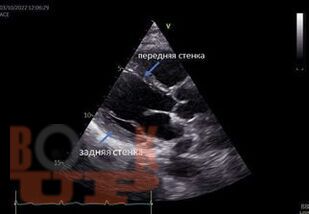

Описаны результаты моделирования гиперупругих свой ств мягких биологических тканей органов человека и животных. Исследовали ткани сердечной мышцы, стенки желчевыводящих протоков, многослойной структуры желудка, периодонтальной связки, слизистой оболочки полости рта, десен, кожи лица и спины, волоса, органов урогенитальной системы (паренхимы почки, мочеточника, мочевого пузыря, женских и мужских репродуктивных органов), ушной раковины и верхних дыхательных путей (носа). В качестве гиперупругих моделей рассмотрены наиболее известные в современной механике деформируемых тел модели: неогуковская, 2-, 3-, 5- и 9-параметрические модели Муни—Ривлина, Огдена, Йео, полиномиальная и модель Веронды—Вестманна. Рассчитаны материальные константы моделей, средние квадратичные отклонения расчетных от экспериментальных данных, коэффициенты корреляции и другие статистические параметры моделей. Расчеты производились в системах компьютерной алгебры MATHCAD 15.0, MATLAB 8.2 и многоцелевом пакете программ ANSYS 2022 R2.